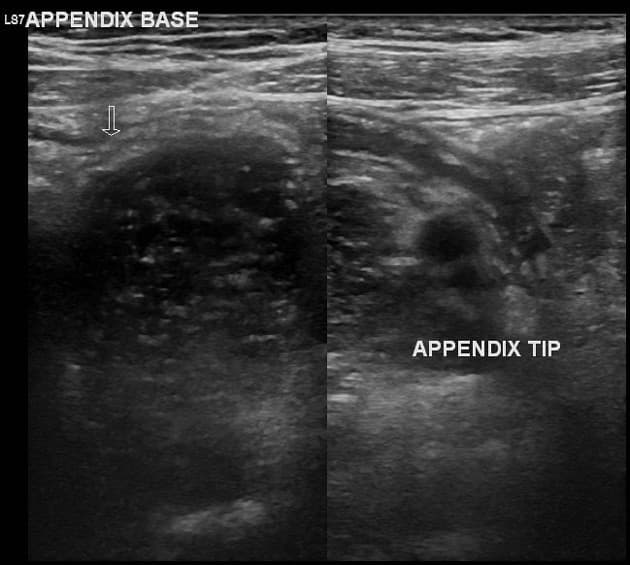

Acute appendicitis in pregnancy (MRI)

Thai 28 tuần, xuất hiện đau hạ sườn phải mới khởi phát.

Quan sát thấy một cấu trúc dạng ống giãn ở vùng hạ sườn phải, kèm tăng tín hiệu T2 xung quanh, gợi ý phù nề và viêm quanh cấu trúc này. Ngoài ra, ghi nhận một viên sỏi trong túi mật.

THẢO LUẬN: Đây là trường hợp viêm ruột thừa cấp ở bệnh nhân mang thai. Sau khi chụp MRI, bệnh nhân đã được phẫu thuật cắt ruột thừa mở, với theo dõi tim thai trước và sau phẫu thuật. Kết quả giải phẫu bệnh cho thấy: Ruột thừa to và giãn Thanh mạc màu xám sẫm đến nâu đỏ Có hiện tượng dính Dịch tiết nhầy mủ lan tỏa Lòng ruột thừa: Giãn Thành dày Các đặc điểm này phù hợp với chẩn đoán viêm ruột thừa cấp trên hình ảnh học. Bệnh nhân dung nạp phẫu thuật tốt, không có biến chứng và hồi phục thuận lợi. Ý nghĩa lâm sàng quan trọng: Trường hợp này nhấn mạnh rằng các bác sĩ lâm sàng và bác sĩ chẩn đoán hình ảnh cần luôn nghĩ đến viêm ruột thừa ở bệnh nhân mang thai có đau hạ sườn phải, vì: 👉 Tử cung mang thai có thể đẩy ruột thừa lên cao, làm thay đổi vị trí giải phẫu bình thường. Điều này có thể gây: Chẩn đoán chậm trễ Hoặc nhầm với bệnh lý gan mật Đồng tác giả: Amira Elfergani

Viêm ruột thừa cấp trong thai kỳ (chụp cộng hưởng từ)